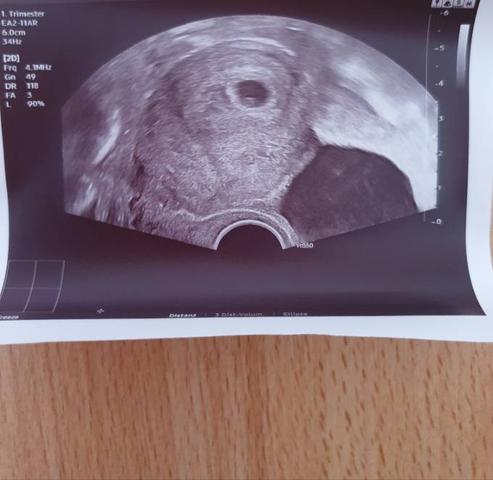

In der 7. SSW kann dann ab einer Größe von 0,7 Zentimetern vom Scheitel bis zum Steiß meist auch eine eindeutige Herzaktion dargestellt werden.

– In der 7. SSW kann bei einer Größe von etwa 0,7 Zentimetern vom Scheitel bis zum Steiß oft bereits eine eindeutige Herzaktion dargestellt werden.

Im Verlauf der Schwangerschaft schreitet die Entwicklung des Embryos jedoch rasch voran. In der 6. SSW kann möglicherweise schon eine Anlage des Embryos am Rand der Fruchthöhle erkennbar sein. In der 7. SSW ist dann in der Regel eine eindeutige Herzaktion zu sehen, wenn das Baby eine Größe von etwa 0,7 Zentimetern hat. In der 8. SSW ist das Baby mit einer Größe von gut einem bis eineinhalb Zentimetern normalerweise gut erkennbar und auch das schlagende Herzchen lässt sich meist deutlich darstellen.

Erst ab der 7. Schwangerschaftswoche wird der Embryo mit einer Größe von etwa 0,7 Zentimetern sichtbar. Hier kann man oft auch schon eine eindeutige Herzaktion erkennen. In der 8. Schwangerschaftswoche ist der Embryo in der Regel gut erkennbar und das schlagende Herzchen lässt sich meist gut darstellen.

7. SSW:

Ab einer Größe von 0,7 Zentimetern vom Scheitel bis zum Steiß kann in der Regel eine eindeutige Herzaktion dargestellt werden.